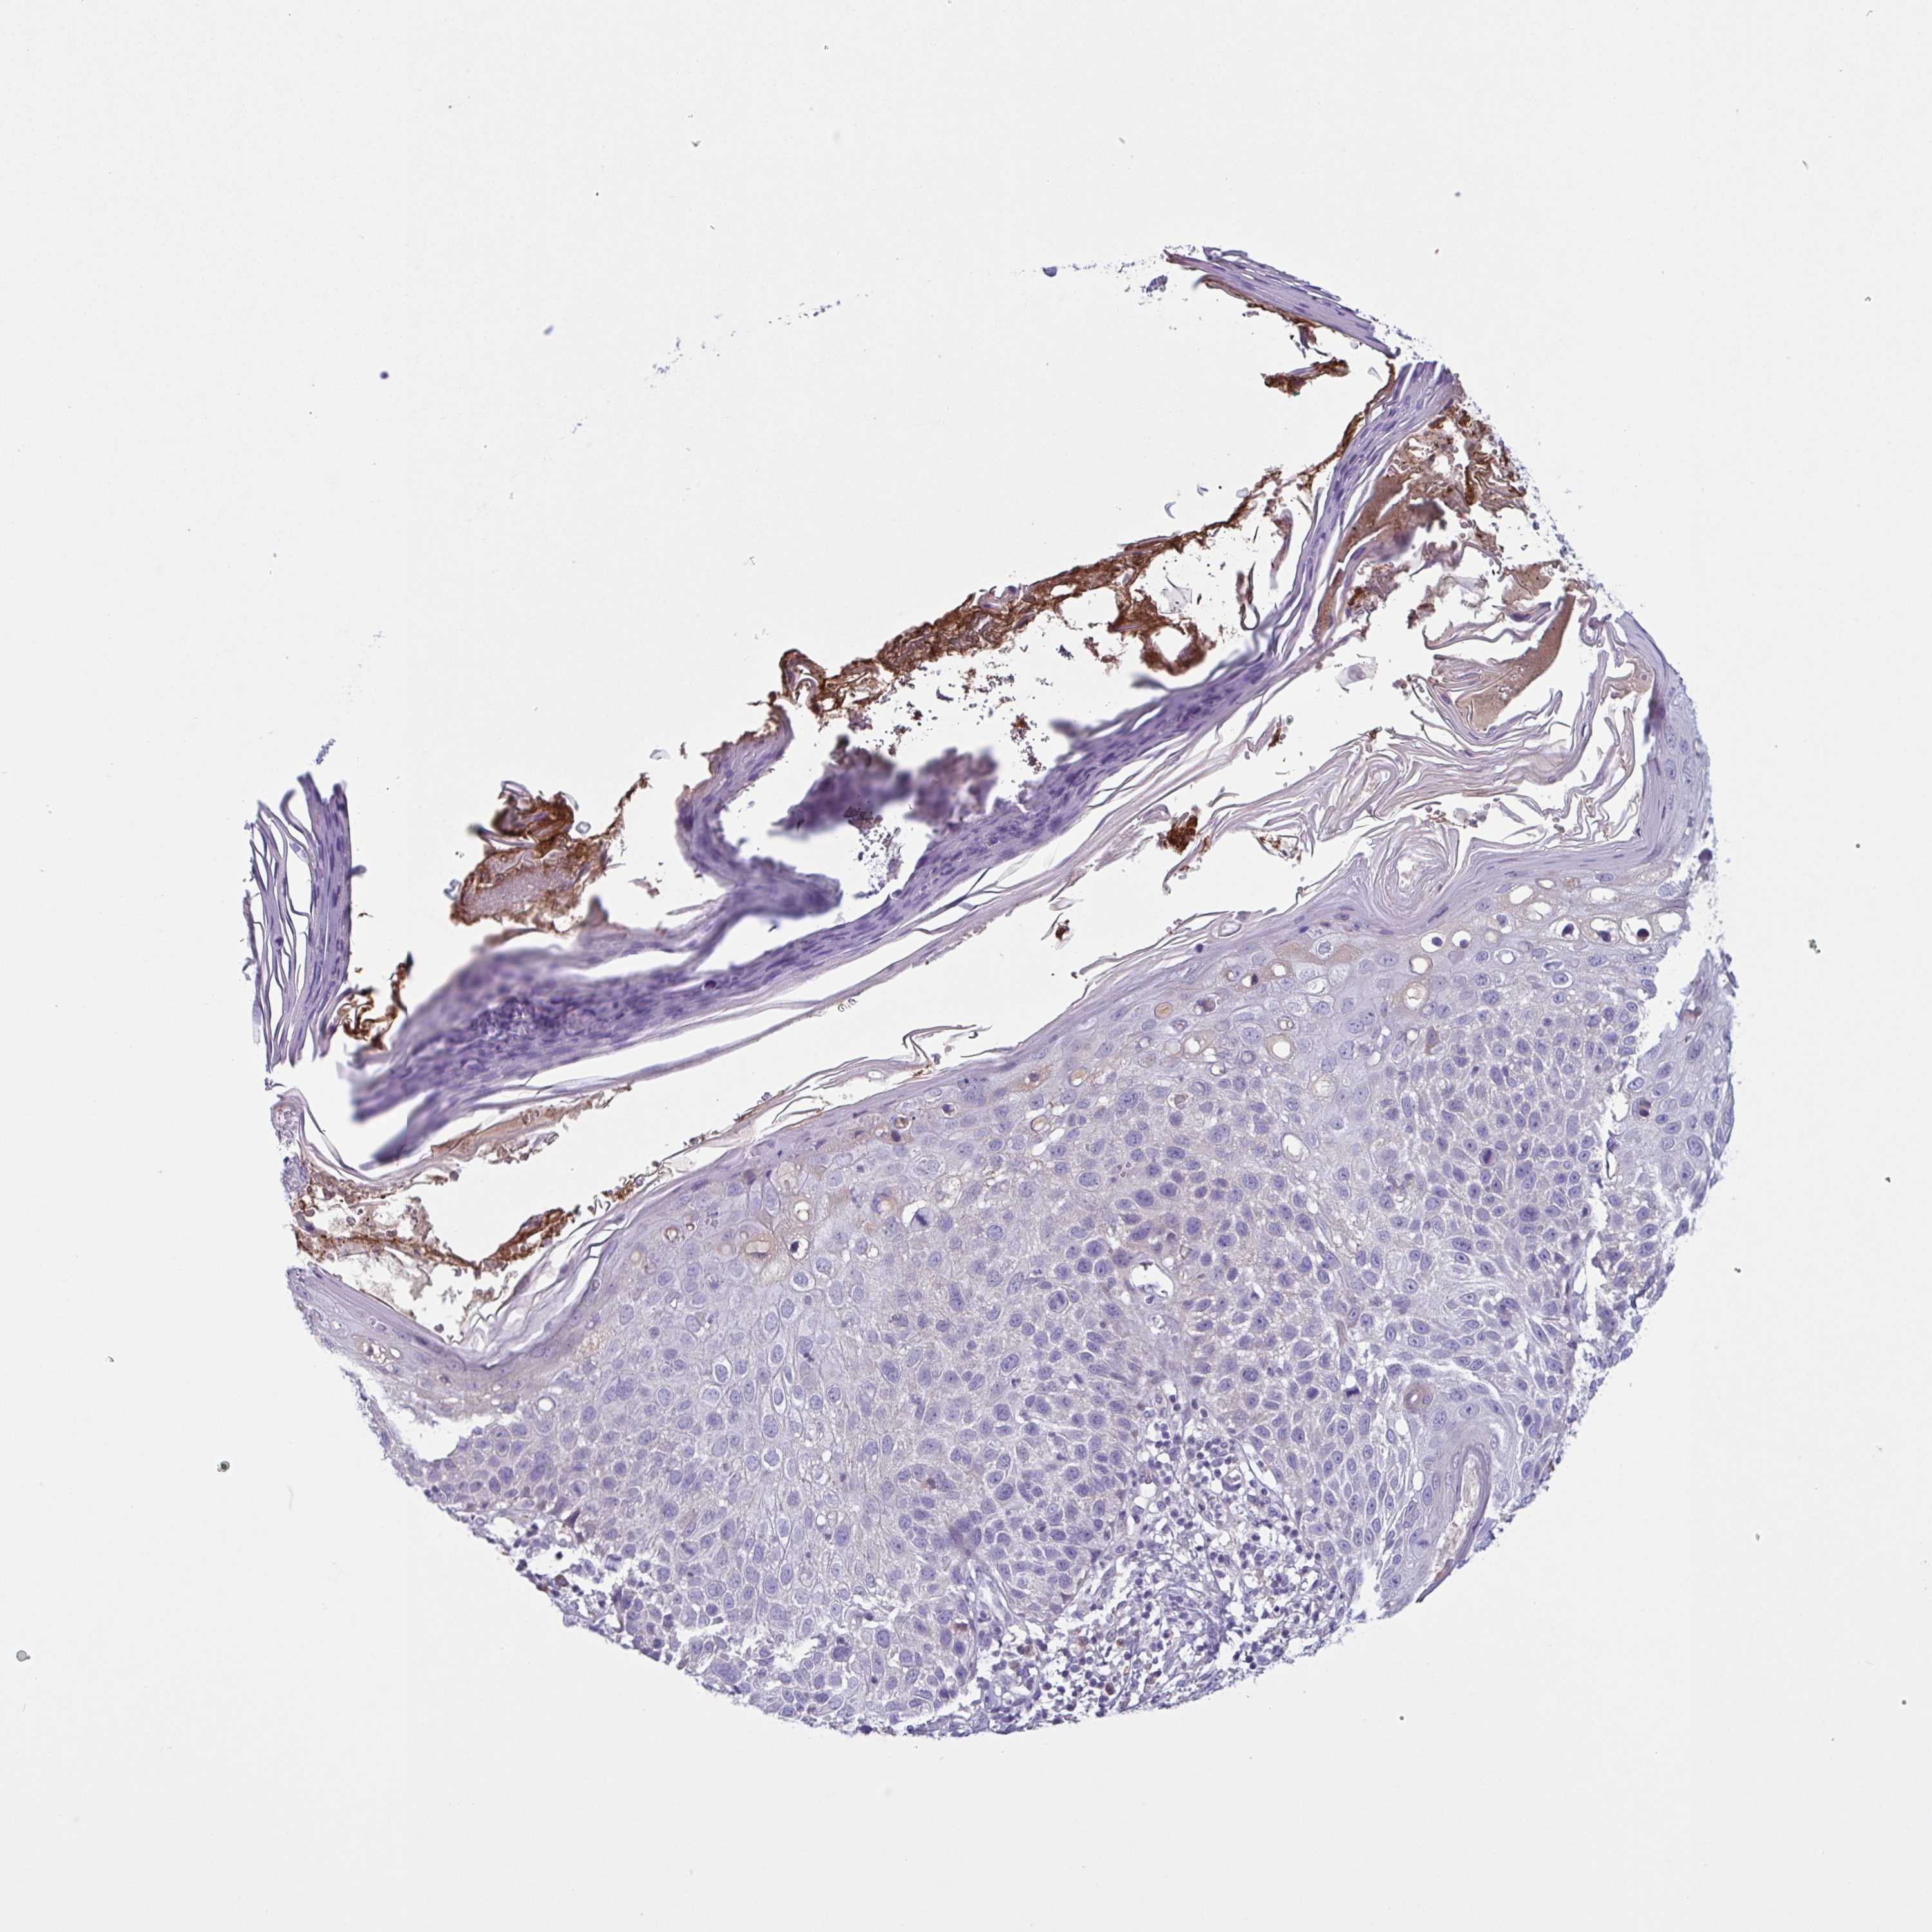

Basal cell and squamous cell cancer

SKIN CANCER - Protein expressioni

A mouse-over function shows sample information and annotation data. Click on an image to view it in a full screen mode. Samples can be filtered based on level of antibody staining by selecting one or several of the following categories: high, medium, low and not detected. The assay and annotation is described here.

Antibody stainingi

Antibody staining in the annotated cell types in the current human tissue is reported as not detected, low, medium, or high, based on conventional immunohistochemistry profiling in selected tissues. This score is based on the combination of the staining intensity and fraction of stained cells.

Each image is clickable and will lead to virtual microscopy that enables deeper exploration of all samples and also displays staining intensity scores, fraction scores and subcellular localization as well as patient and tissue information for each sample.

Antibody HPA003827

Antibody HPA052139

Squamous cell carcinoma, NOS

Basal cell carcinoma